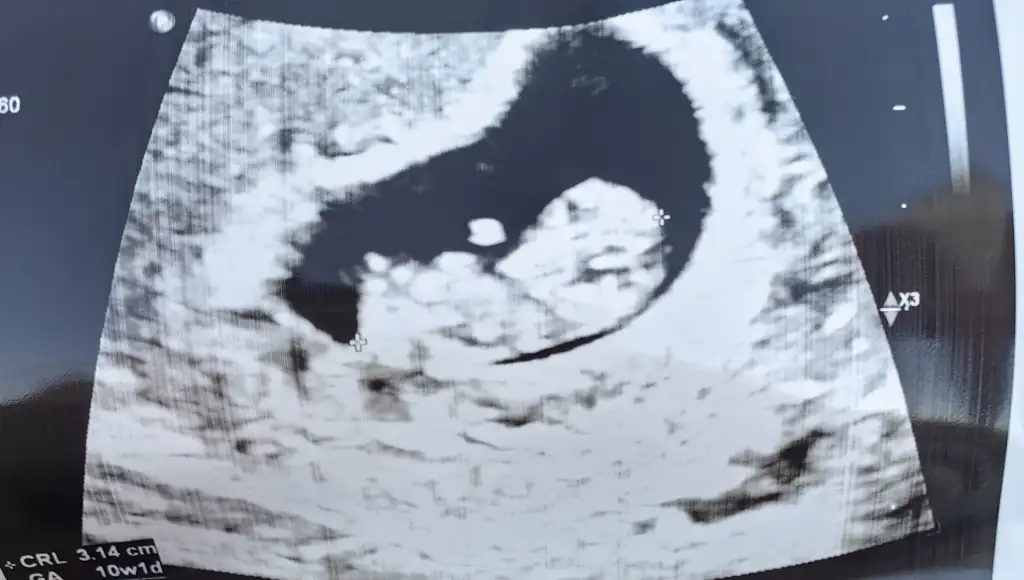

Kalp atisina gidince peki doktor ultrasondan crl olcumuyle yani embriyonun kac haftalik oldugunu direk cihazdan tespit edebiliyor mu 8+0 da gidecegim 7+5 e cagirdi bende iki gun daha duruyum diyorum 8 olsun vajinadan degil karindan sesi duyulsun diye

Evet kalp atışı alındığında zaten en net sonuç çıkıyormuş hafta olarak benim geç döllenme olmuş en son kalp atışında söylendi kaç haftalık olduğu mesela ☺️

Bugün 8+5 im kalp atışını duyduk.🌸